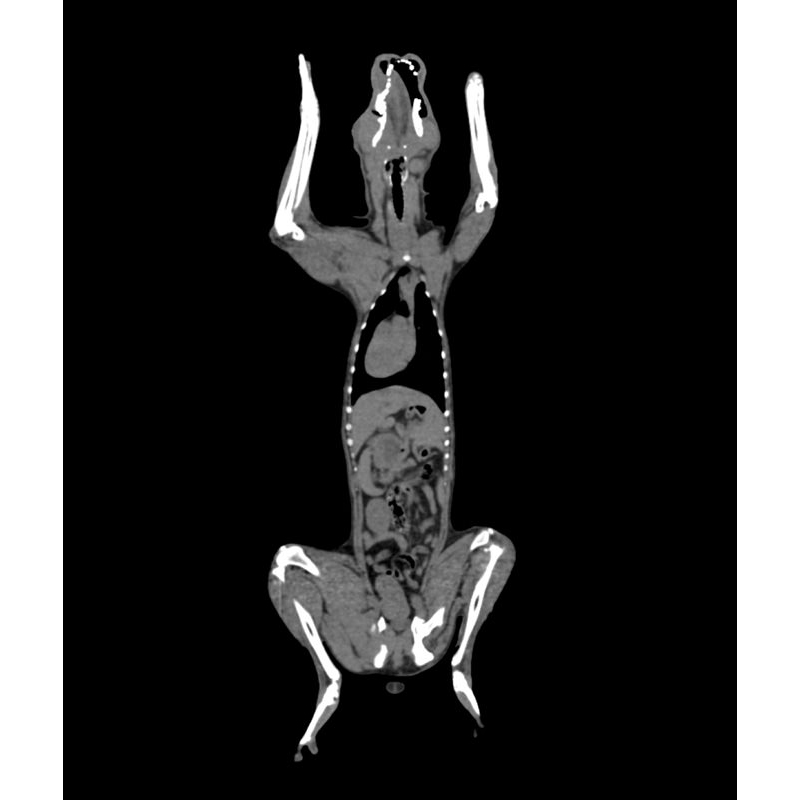

Fantom zagotavlja realistično simulacijo psa brez kontrastnega sredstva. Kosti in mehka tkiva so prikazana verodostojno z realističnimi vrednostmi CT za vsa tkiva pri 120 kVp napetosti cevi v CT. Zračni prostori so zapolnjeni s celuloznim polimernim kompozitom s približno -80 Hounsfieldovimi enotami.

Če se bo fantom uporabljal predvsem pri drugih napetostih cevi (npr. 100 kVp), se lahko po potrebi ustrezno prilagodi kalibracija vrednosti CT ? Fantom zagotavlja tudi realistične kontraste tkiv pri rentgenskem slikanju.

Velikost: 26x15x80 cm